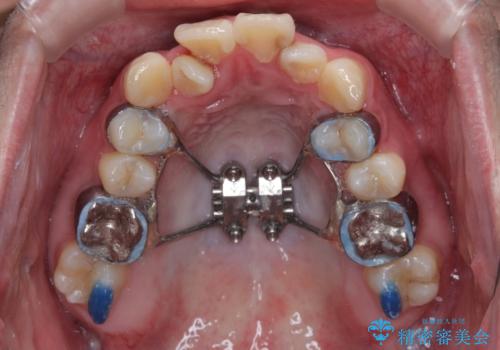

初診時の状態

・上下ともに歯がきれいに並びきらず、がたつきが見られました。

・上下の前歯の中心(正中)がずれています。

・特に上顎の幅が狭いため、下顎の歯列も内側に入り込み、歯が並ぶスペースが不足していました。

治療方針

このような歯列の狭さに起因するデコボコを改善するために、**MARPE(骨に固定する上顎急速拡大装置)**を使用して、上顎の横幅を拡大し、これにより歯が並ぶためのスペースを確保し、メタルブラケットを用いて歯列を整えていく計画としました。